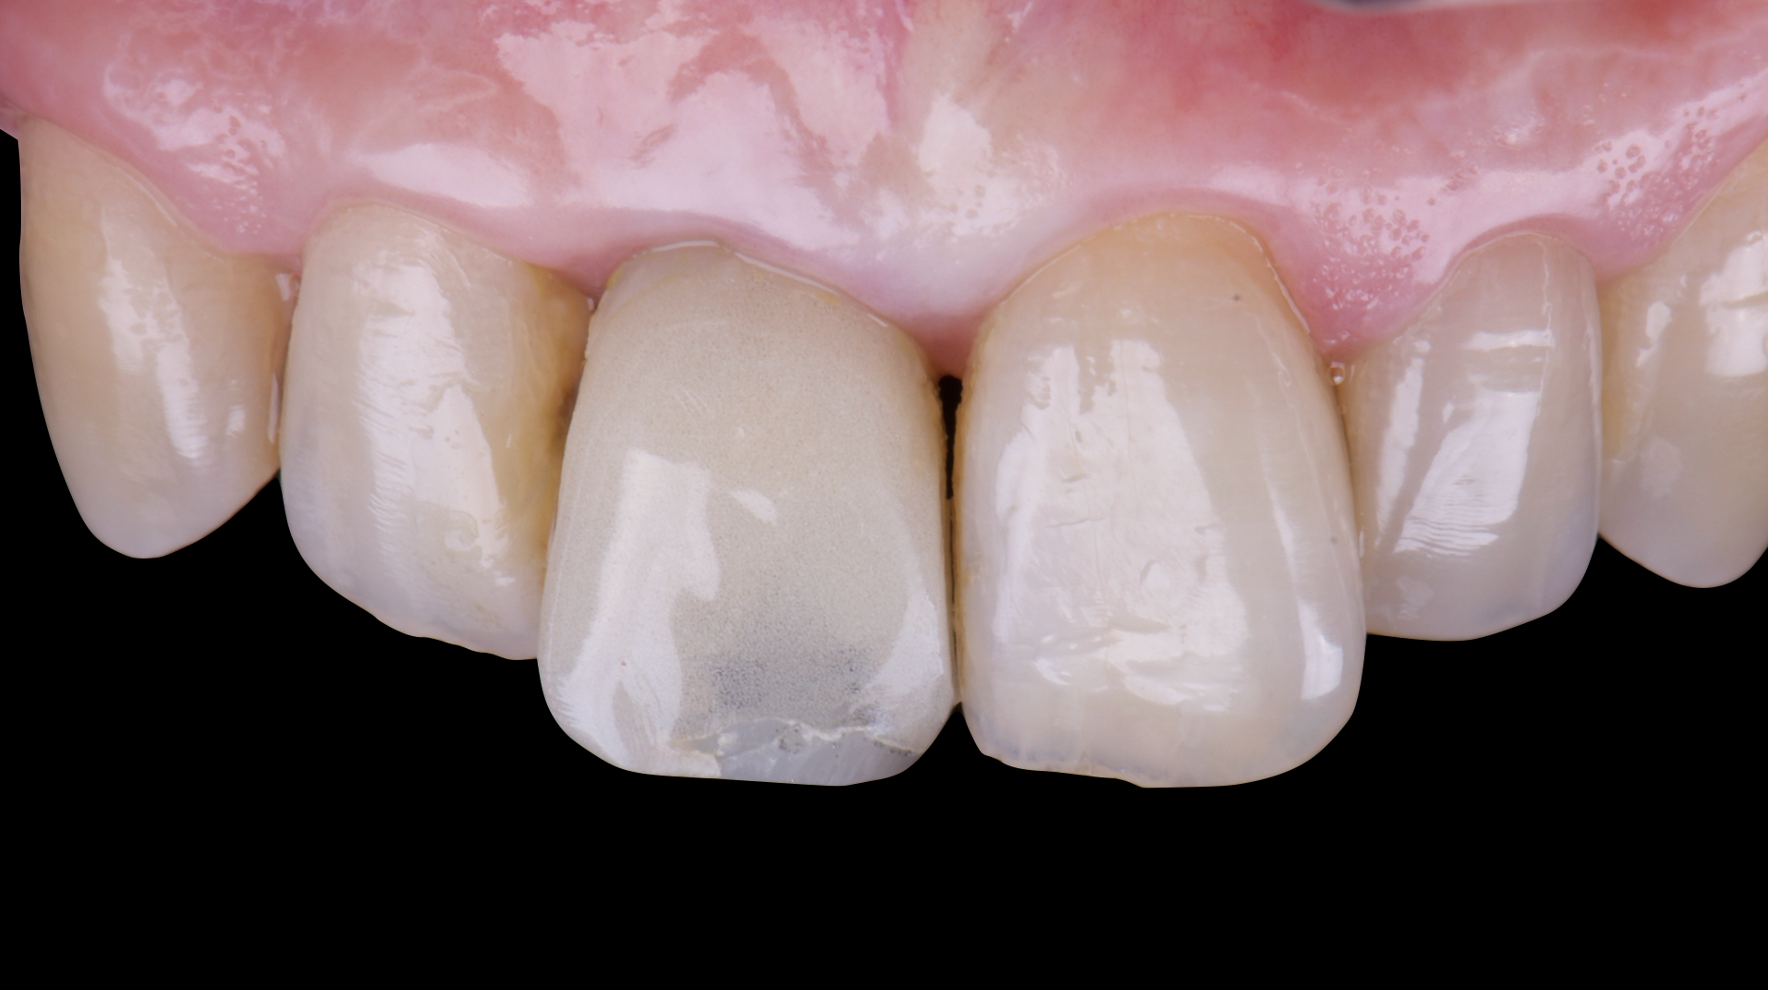

After an appropriate healing period, the definitive prosthesis was planned and delivered. A screw-retained zirconia crown was fabricated to ensure long-term durability, optimal esthetics, and retrievability. Zirconia was selected for its mechanical strength and excellent esthetic properties, blending seamlessly with the adjacent natural dentition in both form and color.

The final crown was designed to maintain the gingival architecture that had been shaped by the provisional. Special attention was paid to the emergence profile, contact points, and translucency to achieve harmony with the patient’s smile. The definitive restoration provided functional stability and esthetic integration, fulfilling the patient’s expectations for a fixed and natural solution.